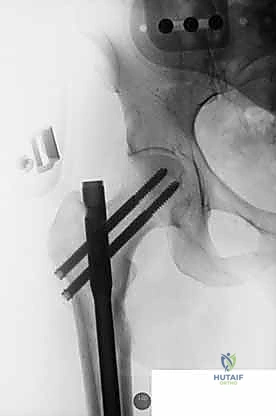

1. المسمار النخاعي الرئيسي (Intramedullary Nail): مسمار طويل يمتد داخل القناة النخاعية لعظمة الفخذ.

2. المسمار الرأسي/العنقي (Cephalic/Lag Screw): مسمار سميك وقوي يمر من خلال الجزء العلوي للمسمار النخاعي، ويدخل في عنق ورأس عظمة الفخذ لتثبيت الكسر الرئيسي.

3. مسامير الغلق السفلية (Distal Locking Screws): مسامير صغيرة تُثبت أسفل المسمار النخاعي لمنعه من الدوران أو الانزلاق داخل العظم.

هذا التصميم العبقري يجعله أقوى نظام تثبيت متوفر حالياً، حيث يمر محور تحمل الوزن عبر المسمار الموجود داخل العظم، مما يجعله مقاوماً للكسر والانحناء، ويسمح للمريض بالاعتماد على ساقه في وقت قياسي.

من خلال ذراع توجيه متصلة بالمسمار الرئيسي، يتم إحداث ثقب في عنق ورأس عظمة الفخذ. يتم إدخال المسمار الرأسي (Cephalic Screw) السميك ليمسك برأس الفخذ بقوة ويسحبه نحو المسمار الرئيسي، مما يضغط الكسر (Compression) ويحفز التئام العظام بسرعة.

6. التثبيت السفلي (Distal Locking)

لضمان عدم دوران العظمة حول المسمار، يتم إدخال مسمار أو مسمارين صغيرين في الجزء السفلي من المسمار النخاعي عبر شقوق جلدية دقيقة جداً (لا تتجاوز 1 سم).